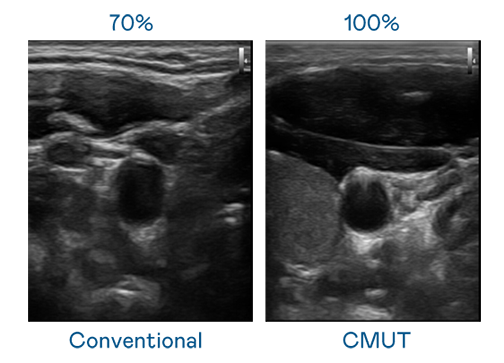

CMUT 技术是一种用电容式微机电元件来产生超音波讯号的技术。与传统 PZT 压电式技术相比,CMUT 频宽增加 30%,更宽频的超音波讯号让影像解析度大幅提升,是实现高影像品质医疗超音波扫描、促进精准医疗发展的关键技术。

超音波影像的解析度高低,首先取决于探头能发出的讯号频宽。FUN88乐天 CMUT 可提供高清晰的超音波讯号,提供高频宽、高灵敏度、影像纹理细节更高的超音波影像,协助医护人员缩短影像判读时间及利用精准的医疗影像进行诊断。